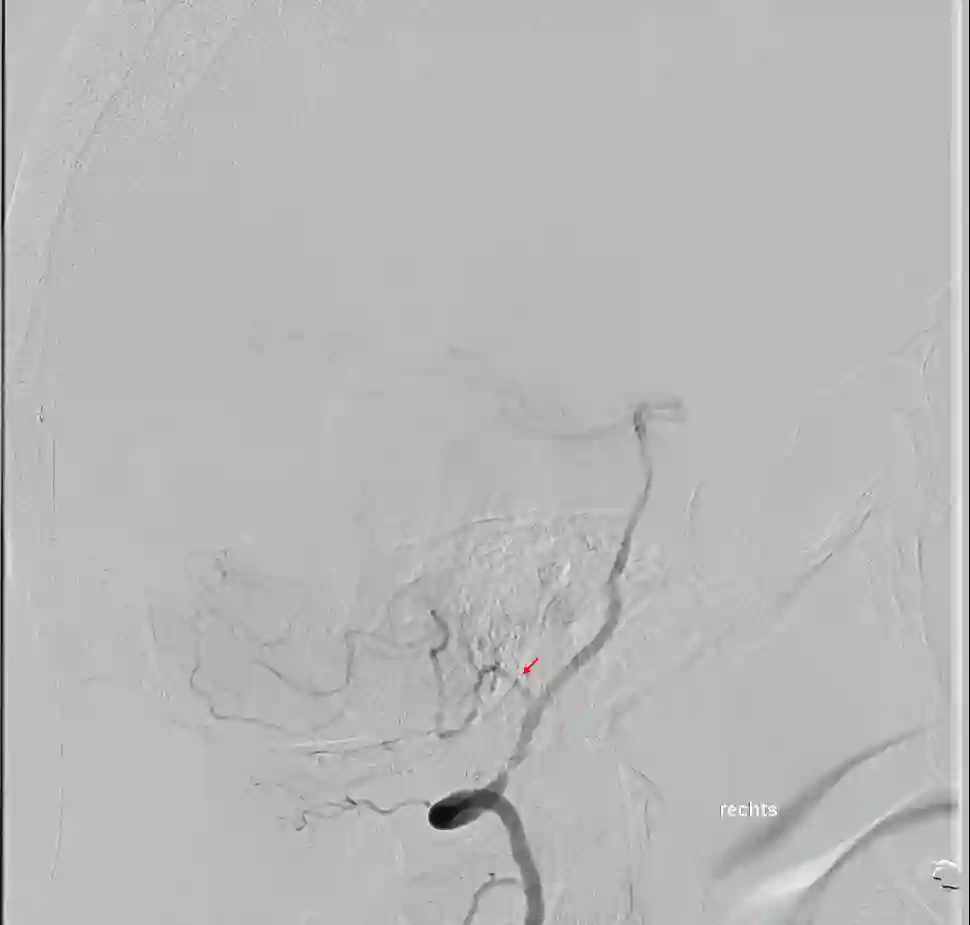

Aneurysmen

Aneurysmen an der PICA stellen 0,49 bis 3 % aller cerebralen Aneurysmen dar [^1] [^6].